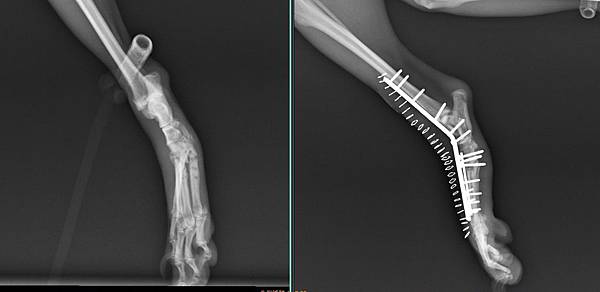

Apple來找小譚醫師的時候

說腳腳之前在南部有手術

但手術後鋼板裸露在外面而且依直流膿

所以來找小譚醫師想辦法

我們先將感染的鋼板移除

花了一個月養好傷口

這時候腳腳呈現一個非常不正常的姿勢無法行走

經過手術後

成功的讓腳腳恢復正常的姿勢

手術後兩周

我們醫療團隊成功的讓Apple恢復走跳的能力